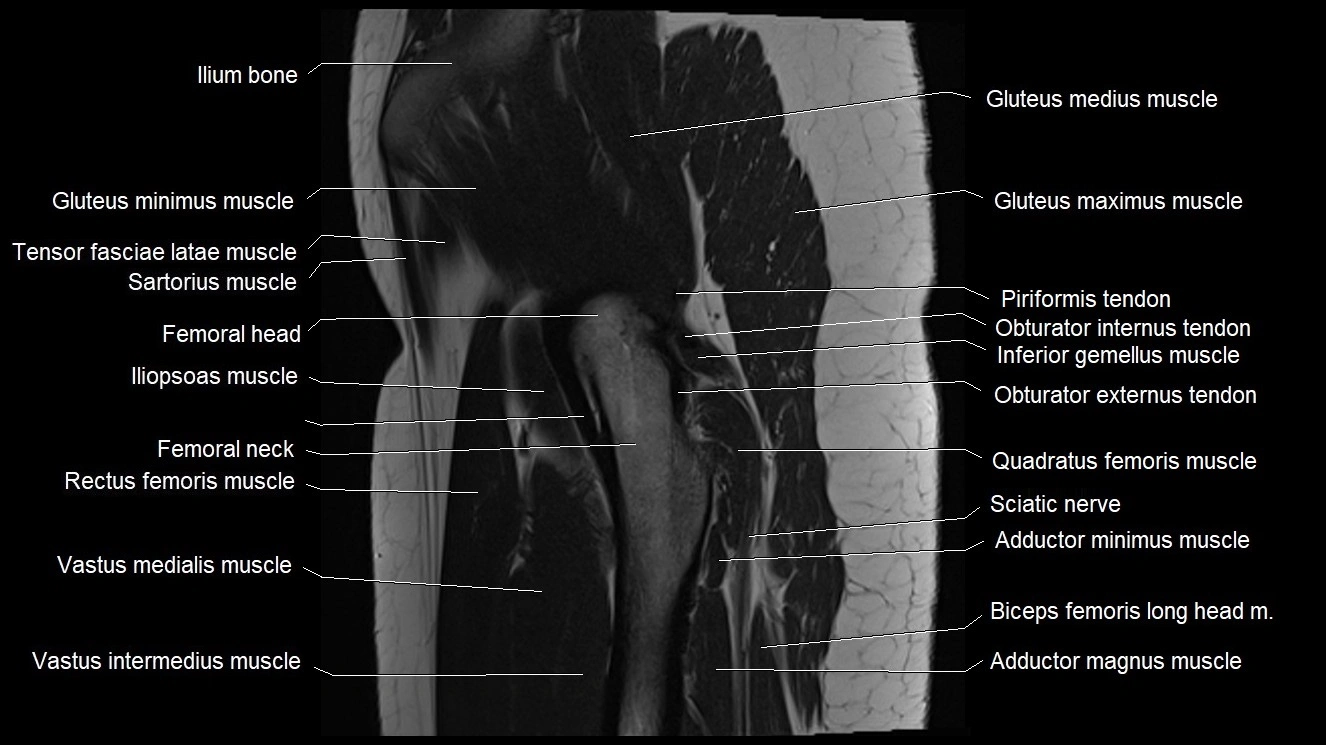

- Gluteus maximus muscle

- Gluteus medius muscle

- Gluteus minimus muscle

- Gluteus minimus tendon

- Iliopsoas muscle

- Inferior gemellus muscle

- Obturator externus tendon

- Obturator internus tendon

- Quadratus femoris muscle

- Rectus femoris muscle

- Sartorius muscle

- Tensor fasciae latae muscle

- Vastus intermedius muscle

- Vastus medialis muscle